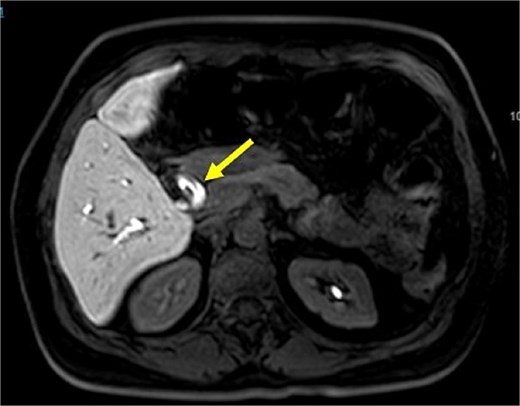

Initial imaging with ultrasound and computed tomography (CT) revealed intrahepatic bile duct dilatation without evidence of stones. Magnetic resonance cholangiopancreatography (Figs 1 and 2) showed a solid intraductal lesion extending from the left bile duct to the common bile duct, raising suspicion for IPNB versus MCN-L. SpyGlass endoscopy confirmed the presence of a solid intraductal tumor. Laboratory findings, including bilirubin, alpha-fetoprotein, and carcinoembryonic antigen, were within normal limits.

Magnetic resonance cholangiopancreatography image common bile duct intraductal tumor, axial view.